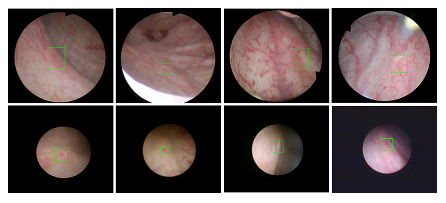

Cableav 医疗机器人研究院—深睿医疗人工智能医学视频联合实验室成立于2018年7月。PI包括来自于交大生医工学院和电院的三位教授,平台建设目标是将人工智能实时地用到临床医学中去,研究方向包括:1. 建立内窥镜人工智能辅助诊断系统,通过对病灶和解剖结构的实时识别来辅助医生更好地进行微创诊断和治疗;2. 以个性化、定量化的精准诊疗技术为研发目标,重点开展医学影像智能诊断、医学可视化及计算机辅助手术规划、AI及大数据分析在临床诊疗流程中的集成应用等方向的研发。试图利用AI技术、大数据分析技术、3D打印技术、虚拟现实及增强现实技术促进临床的影像诊断、治疗方案设计、预后预测分析等诊疗环节的智能化提升与技术变革;3. 面向运动医学康复、神经退行性疾病量化诊断,以及其他与人体运动相关的疾病诊疗、康复应用,开展视觉三维人体运动的测量、分析与识别研究,通过基于深度学习的视觉检测识别以及相关大数据分析,为相关疾病的诊疗和康复提供AI辅助。具体临床应用包括:关节镜手术术后康复指导和评估、帕金森病的量化诊断、精神疾病的量化诊断与评估、儿童异常行为分析等。

近年来,联合实验室发展了泌尿镜手术实时识别技术,人体姿态精确识别技术,另外围绕小儿先心病手术、肝癌消融手术、数字口腔诊疗的智能化提升等内容进行应用研发。